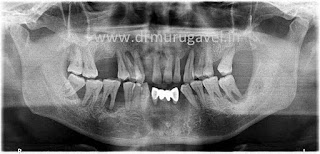

Pre treatment xray showing severe bone loss around the teeth due to gum disease

POST TREATEMENT OPG SHOWING BASAL IMPLANTS